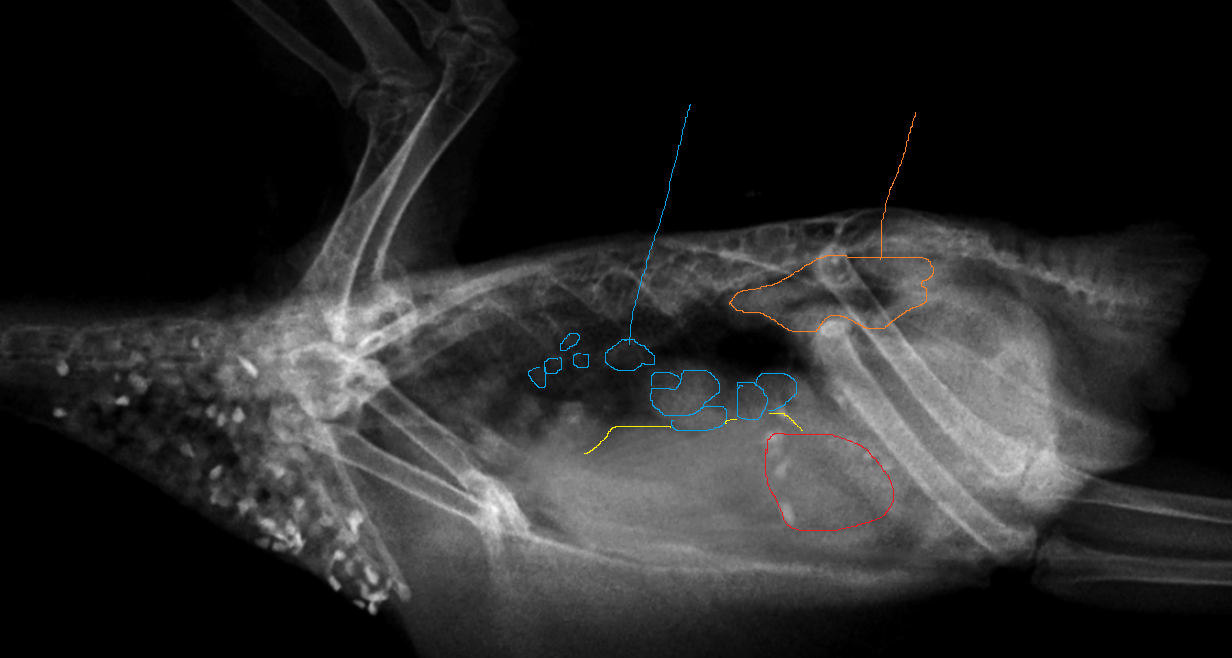

Zosia Опубликовано 4 октября, 2024 #395 Опубликовано 4 октября, 2024 Птицу даль. По снимку- 1.Почки окружены фибриновой капсулой, что говорит о длительном воспалении В ОКРУЖАЮЩИХ тканях. Капсула толстая. Отмечено оранжевой линией. 2.Множество кист или фолликул на стадии формирования яйца, различного размера, не имеющих ровной поверхности- что говорит так же о наличии хронического воспалительного процесса и откладывания фибрина (или гиалина) на поверхности и, вероятно,пропитывании объектов. Отмечены голубым. 3.Смещен мускульный желудок, видимо этими кистами.Отмечен красным. 4.Печень так же под физическим воздействием кист (по типу краш-синдрома) Дистальный край отмечень желтым. 5.На правой лапе- следы неравномерной плотности костных тканей- возможно перелом, старый или патологический. Отмечен зеленым. Так же отмечается неравномерная плотность трубчатых костей крыльев. Почти наверняка на вскрытии возможно обнаружить хроническое воспаление , с тяжами, органов брюшной полости. Пликистоз с фиброзом яичника, фиброзом почет (почек). Причина- первичные гормональные нарушения (есть ли опухоль- только на вскрытии можно увидеть), с присоединившейся инфекцией на основе УПБ. Возможен ателектаз легких, или фиброз легких (на снимке не могу достоверно это сказать). Возможность выживания- на данной стадии невозможно. Принципиально- да, при проведении гормональной терапии, направленной на полное прекращение овуляции. Отмечу, что таковая терапия не всегда успешна (проводится мегестролом ацетатом с параллельным использованием ГКС, постоянными курсами, или ведением раз в 8 месяцев супрелорина подкожно). 4